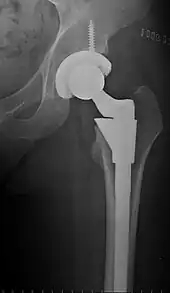

Cement-free implant sixteen days after surgery. Femoral component is cobalt chromium combined with titanium which induces bone growth into the implant. Ceramic head. Acetabular cup coated with bone growth-inducing material and held temporarily in place with a single screw.

The prosthetic implant used in hip replacement consists of three parts: the acetabular cup, the femoral component, and the articular interface. Options exist for different people and indications. The evidence for a number of newer devices is not very good, including: ceramic-on-ceramic bearings, modular femoral necks, and uncemented monoblock cups.[76] Correct selection of the prosthesis is important.